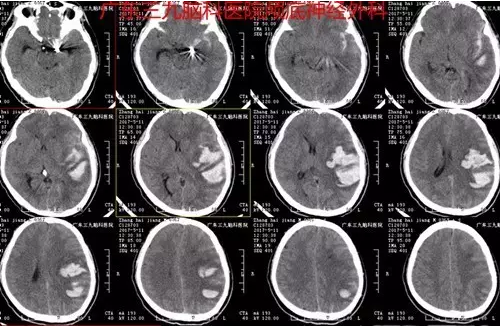

图5:出院后1月患者突发肢体乏力、言语不清,急查头颅CT提示颅内出血

图6:再次行造影提示左侧颈内动脉末端动脉瘤栓塞术后改变,颈内末端可见弹簧圈形态改变、移位,近端可见一囊状动脉瘤大小约2.0mm*4.0mm,朝后生长